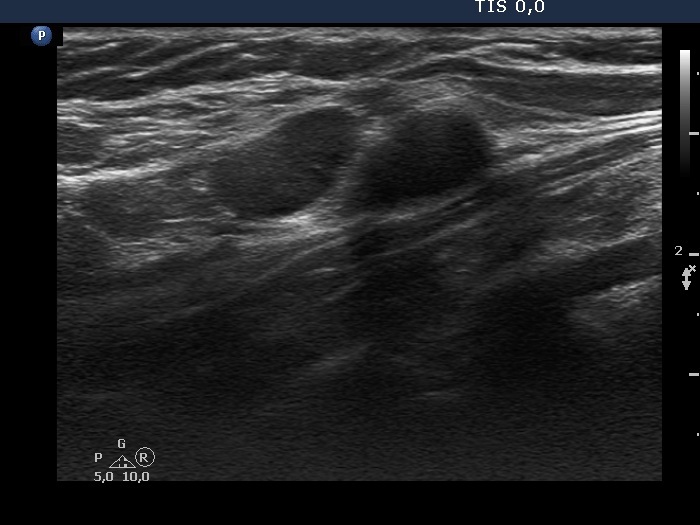

Second examination 3 years later (second, fourth and sixth rows of images):

Ultrasonography. Compared with the previous examination, both the number and the size of discrete lesions in the thyroid have increased.